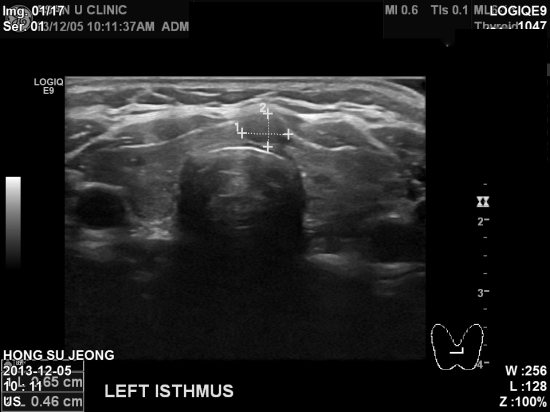

아산유외과 개원 후 14번째 갑상선암 진단.

PET scan이라는 검사로 갑상선에 비정상 소견보인다고 의뢰되신 61세 여자분입니다.

0.84cm정도의 작은 혹이나

가장 좁은 부분인 협부에 있어 수술이 빨리 이루어져야하는 경우에 해당합니다.

중심핵생검으로 갑상선의 유두암 진단되셨으며

수술예정입니다.